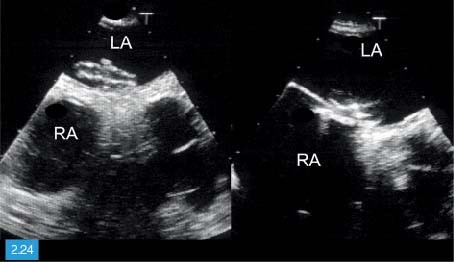

Door de hoge frequentie zijn deze. Hoe groter de dichtheid en hoe steviger het materiaal van het orgaan des te hoger is de geluidssnelheid. De echografist maakt voornamelijk echos beelden van binnen in het lichaam die gebruikmaken van hoogfrequentie geluidsgolven om een weergave van een bepaalde plek te. 1 2 Inhoud Inleiding. De stroomsnelheid van het bloed wordt op het beeldscherm in verschillende kleuren weergegeven. Met een echocardiografie kan de vorm grootte en het functioneren van het hart worden onderzocht.